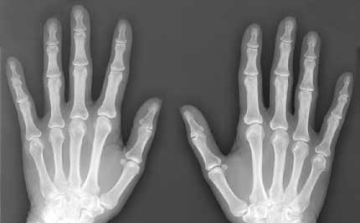

Kézközépcsonttörést szenvedett Nagy László, a Veszprém kézilabdázója

Eltört a kézközépcsontja Nagy Lászlónak, a Telekom Veszprém kézilabdázójának.